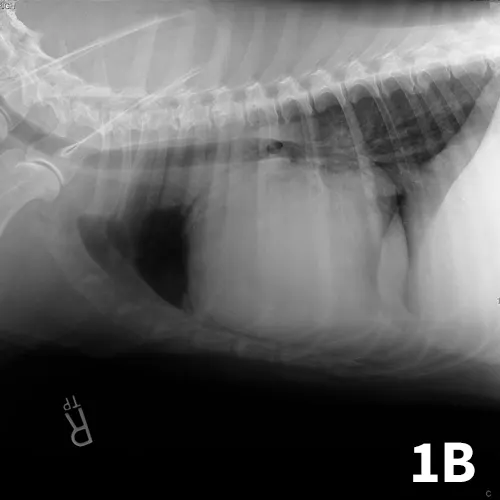

Diagnosis may be based on clinical signs, thoracic radiographs documenting a globoid cardiac silhouette (Figure 1), or ultrasonography (Figure 2). If possible, a complete cardiac ultrasound examination should be performed before pericardiocentesis, as the effusion will help delineate a mass.

Ventrodorsal (A) and right lateral (B) thoracic radiographs showing a globoid heart.